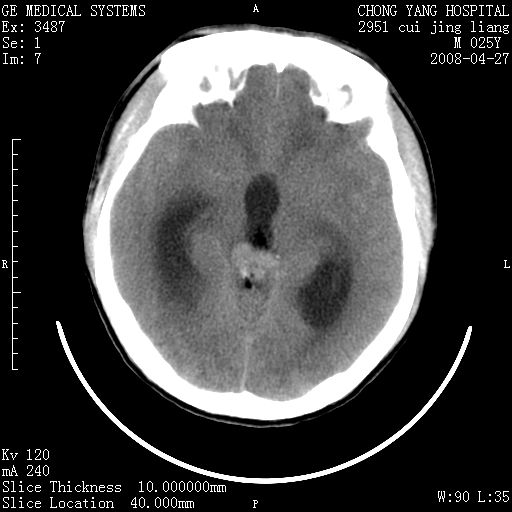

以下是引用余辉在2008-4-27 17:08:00的发言:[br]支持考虑松果体区畸胎瘤伴梗阻性脑积水,左侧室前角还有脂液滴?

以下是引用王仕学在2008-4-27 16:25:00的发言:[br]软组织肿块+脂肪球,考虑松果体区畸胎瘤可能性大。

以下是引用随光逐影在2008-4-27 20:13:00的发言:[br]1)考虑为:第三脑室后部、松果体区畸胎瘤。2)脑积水(梗阻性)。

以下是引用jinguoji在2008-4-27 23:41:00的发言:[br]考虑松果体区肿瘤引起梗阻性脑积水。